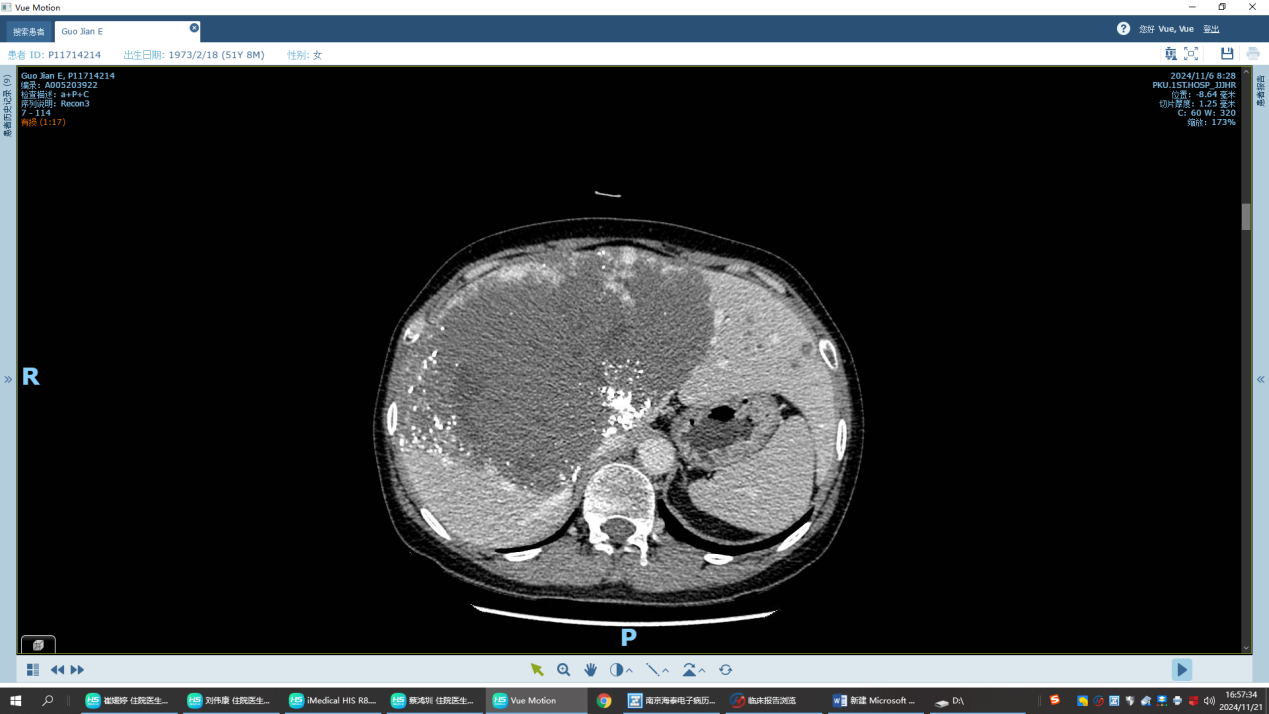

6月3日,肝胆胰外科为患者组织了一次全院会诊,最终认为患者肝血管瘤体积巨大,存在极高出血及感染风险,建议郭女士首先至介入血管外科对肿瘤进行栓塞,待肿瘤体积缩小后再由肝胆胰外科完成手术切除。从炎夏至初秋,患者先后在我院介入血管外科王健副主任处接受了四次TACE治疗,术后CT提示肿瘤体积较前缩小,强化成分明显减少。多学科讨论认为时机已到,可考虑入院手术。

四次TACE治疗后